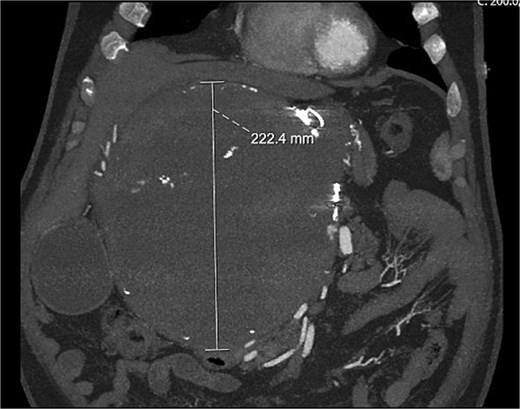

A computed tomography (CT) aortogram performed to exclude an aortic dissection detected a large right upper quadrant lesion measuring 230 × 178 × 224 mm (Fig. 1). A targeted multiphase CT abdomen and pelvis again revealed a large mass with heterogeneous internal attenuation and high peripheral attenuation. A small feeding vessel was identified inferiorly adjacent to its junction with the common hepatic artery. Significant mass effect on surrounding structures was demonstrated with partial compression and displacement of the pancreas, spleen, duodenum, liver, aorta, and inferior vena cava.